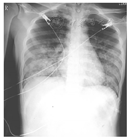

7月10日(化疗后第8天)血常规:白细胞计数1.58 × 109/L,中性粒细胞计数1.09 × 109/L,血红蛋白61 g/L,血小板计数17 × 109/L,当日11:20患者出现咳嗽,咳少量白痰带血丝,余未见出血,亦无呼吸气促等其他不适,予完善G试验,并予止咳糖浆对症处理。18:30患者咳嗽加重,并咳血2次,量约15 ml,予床边监测,血压118/72 mmHg(1 mmHg=0.133 kPa),脉搏105次/min,动脉血氧饱和度0.71,双侧中下肺可闻及细啰音,立即予4 L/min中流量给氧,动脉血氧饱和度升至0.94,查血常规:白细胞计数3.34 × 109/L,中性粒细胞计数3.1 × 109/L,血红蛋白50 g/L,血小板计数10 × 109/L;凝血功能:活化部分凝血活酶时间正常,凝血酶原时间18.6 s,纤维蛋白原3.65 g/L,降钙素原0.24 μg/L,C反应蛋白38.87 mg/L,B型脑钠肽前体1 503 ng/L,血气分析提示Ⅰ型呼吸衰竭,胸腹CT可见右肺上叶后段、左肺上叶尖后段、左肺舌段、右肺中叶、双肺下叶弥散多发斑片状阴影及磨玻璃影,边缘模糊,腹部重要脏器未见明显异常,考虑双肺多发炎性反应,并肺泡内积血(图2)。诊断:弥漫性肺泡出血。立即停用维甲酸、重组人粒细胞刺激因子及重组白细胞介素-11,予甲泼尼龙琥珀酸钠500 mg静脉滴注,并予无创呼吸机辅助通气,头孢哌酮钠舒巴坦钠、利奈唑胺、伏立康唑抗感染,垂体后叶素止血,以及成分血输注。次日患者临床情况稳定,床旁胸片与CT对比大致相似,完善床边纤维支气管镜检查并行肺泡灌洗,镜下各支气管未见出血,多肺段灌洗见血性灌洗液,常规留取标本送检及培养。